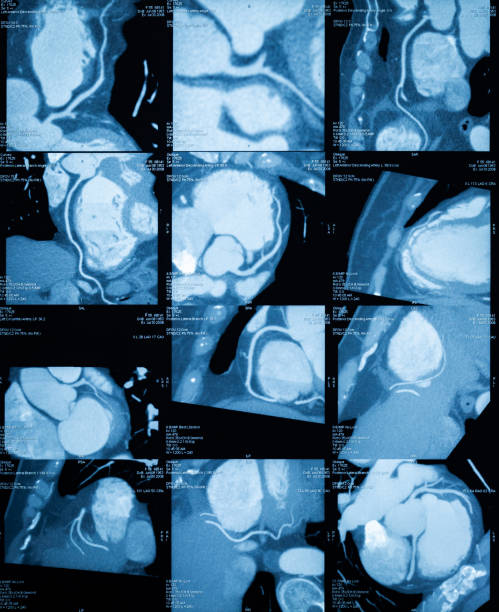

Мы применяем современные мультичастотные ультразвуковые датчики, благодаря которым врач получает изображения с высокой детализацией и точную информацию о состоянии сердечно-сосудистой системы. Динамические и трехмерные модели сердца создаются благодаря режимам 3D и 4D. Врач получает возможность детально изучить работу клапанов, сократительную функцию миокарда и кровоток в реальном времени. Такие технологии позволяют обнаружить даже мелкие отклонения, которые могут быть упущены при стандартных методах исследования. Кроме того, эти режимы незаменимы при планировании хирургических вмешательств и мониторинге их результатов.

УЗИ сердца, или эхокардиография, проводится в положении пациента на спине, иногда на левом боку для улучшения визуализации. Врач наносит специальный гель на грудную клетку, чтобы улучшить контакт с ультразвуковым датчиком. Затем датчик поочередно размещается в разных точках на груди, направляя ультразвуковые волны на сердце для создания изображений. Исследование позволяет оценить размеры и функцию сердца, работу клапанов и кровоток в сердечных камерах. Процедура безболезненная и обычно занимает около 15-30 минут, после чего врач интерпретирует полученные данные и выдает заключение.

Результаты УЗИ сердца

После завершения процедуры врач-диагност в «ИРАМЕД» анализирует результаты исследования. Он также оценивает работу сердечных клапанов, функциональные структуры и состояние мягких тканей. На основе этих данных врач определяет возможные патологии.

После ультразвукового исследования сердца пациент в «ИРАМЕД» получает эхокардиограмму, а также заключение врача-диагноста. В протоколе ЭхоКГ указываются нормы, соответствующие определённой половозрастной группе, которые учитываются при составлении заключения и сопоставляются с полученными результатами.